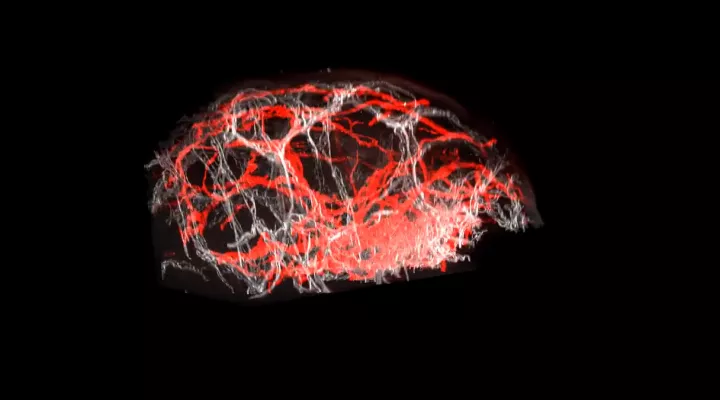

3D-Rekonstruktionen von Haut

Gesunde Haut

3D-Rekonstruktion von gesunder Haut, die die Gefässarchitektur der Blut- und Lymphgefässe zeigt. Die Blutgefässe sind weiss markiert, Lymphgefässe rot, die grünen Punkte stellen Bereiche mit Lymphklappen dar.